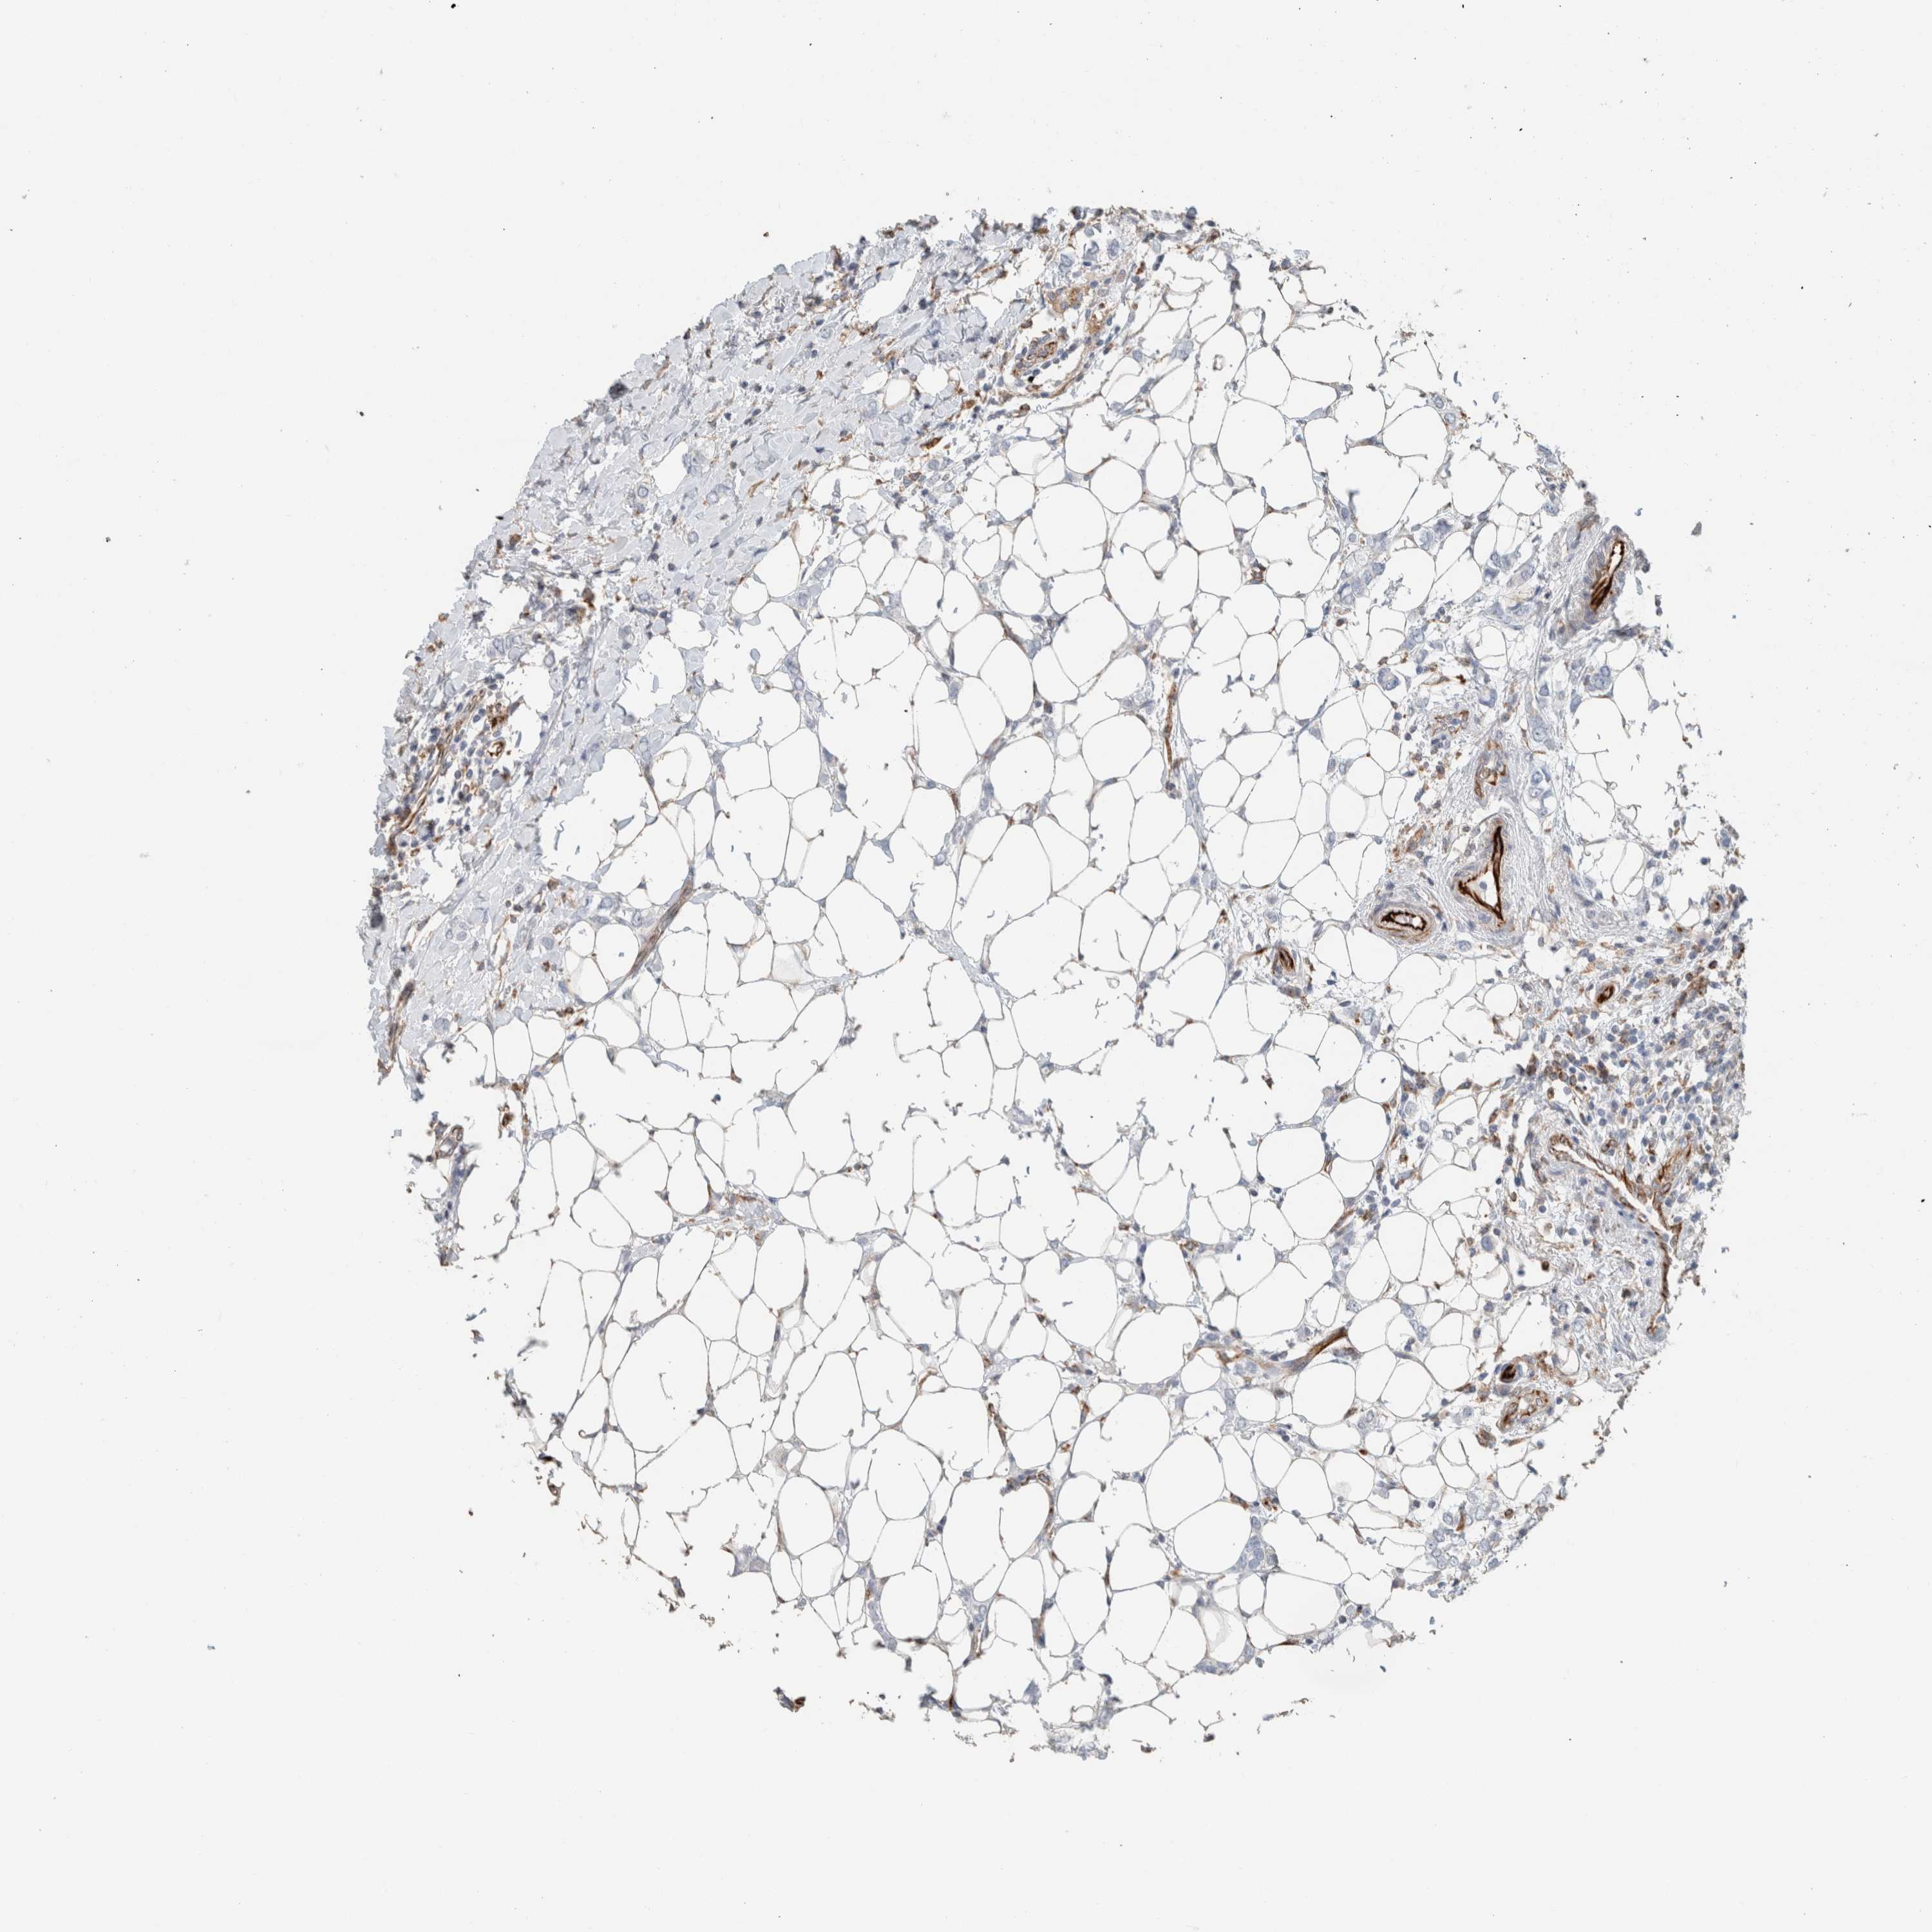

CANCER BREAST CANCER Show tissue menu

BRCA TCGA BRCA VALIDATION PROTEIN EXPRESSION